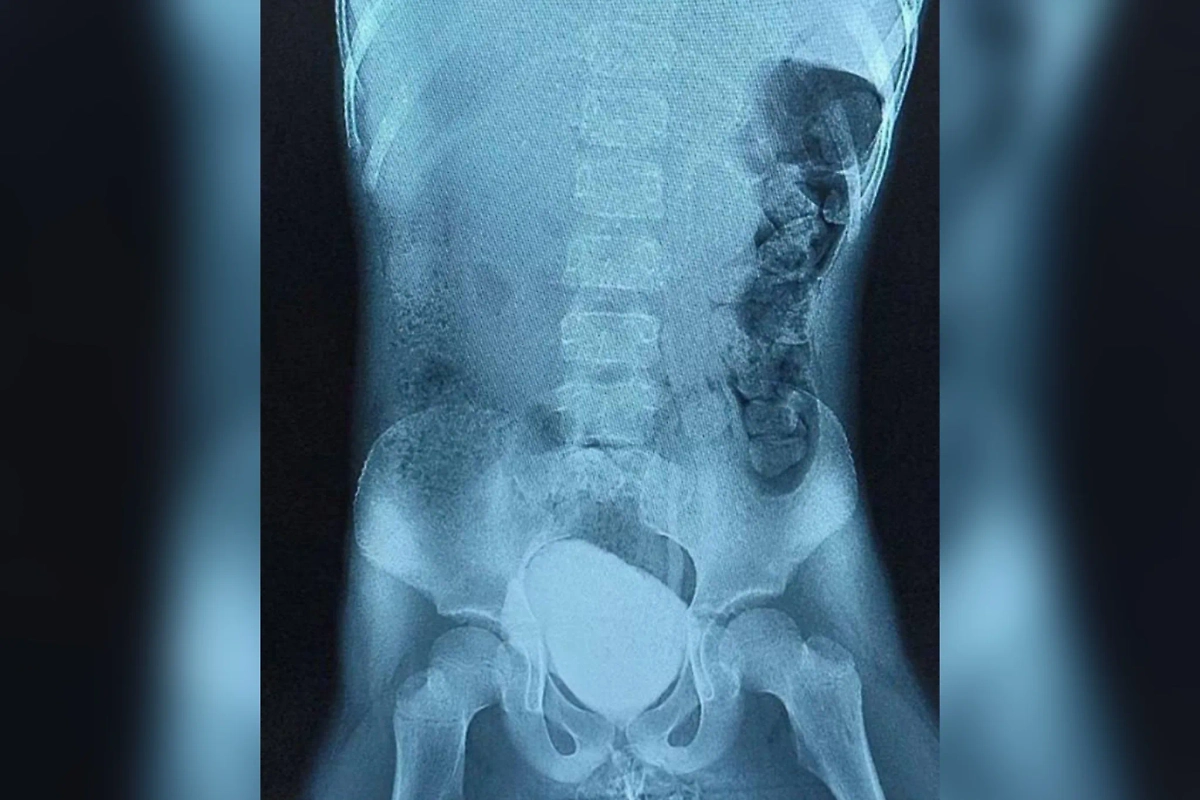

Врачи в Подмосковье успешно провели операцию семилетней девочке с врождённым дефектом спинного мозга, который привёл к аномально малому размеру мочевого пузыря (30 мл). Из-за этого ребёнок страдал от недержания и не мог посещать школу. После вмешательства в Детском клиническом центре им. Л. М. Рошаля орган удалось привести к нормальным размерам, рассказали в пресс-службе Минздрава.

«Мы столкнулись с уникальным случаем поражения нервных окончаний, из-за которых мочевой пузырь находился в постоянном спазме. Мы провели операцию, в ходе которой ввели ботулотоксин в 40 точек стенки мочевого пузыря. Это позволило расслабить мышцы и нормализовать процесс наполнения органа», — рассказал заведующий отделением урологии и андрологии Фёдор Напольников.

Результат превзошёл все ожидания: уже через неделю после вмешательства объём мочевого пузыря увеличился до нормальных 180 мл. Несмотря на необходимость реабилитации, девочка уже чувствует себя полностью здоровой и готова вернуться к учёбе.